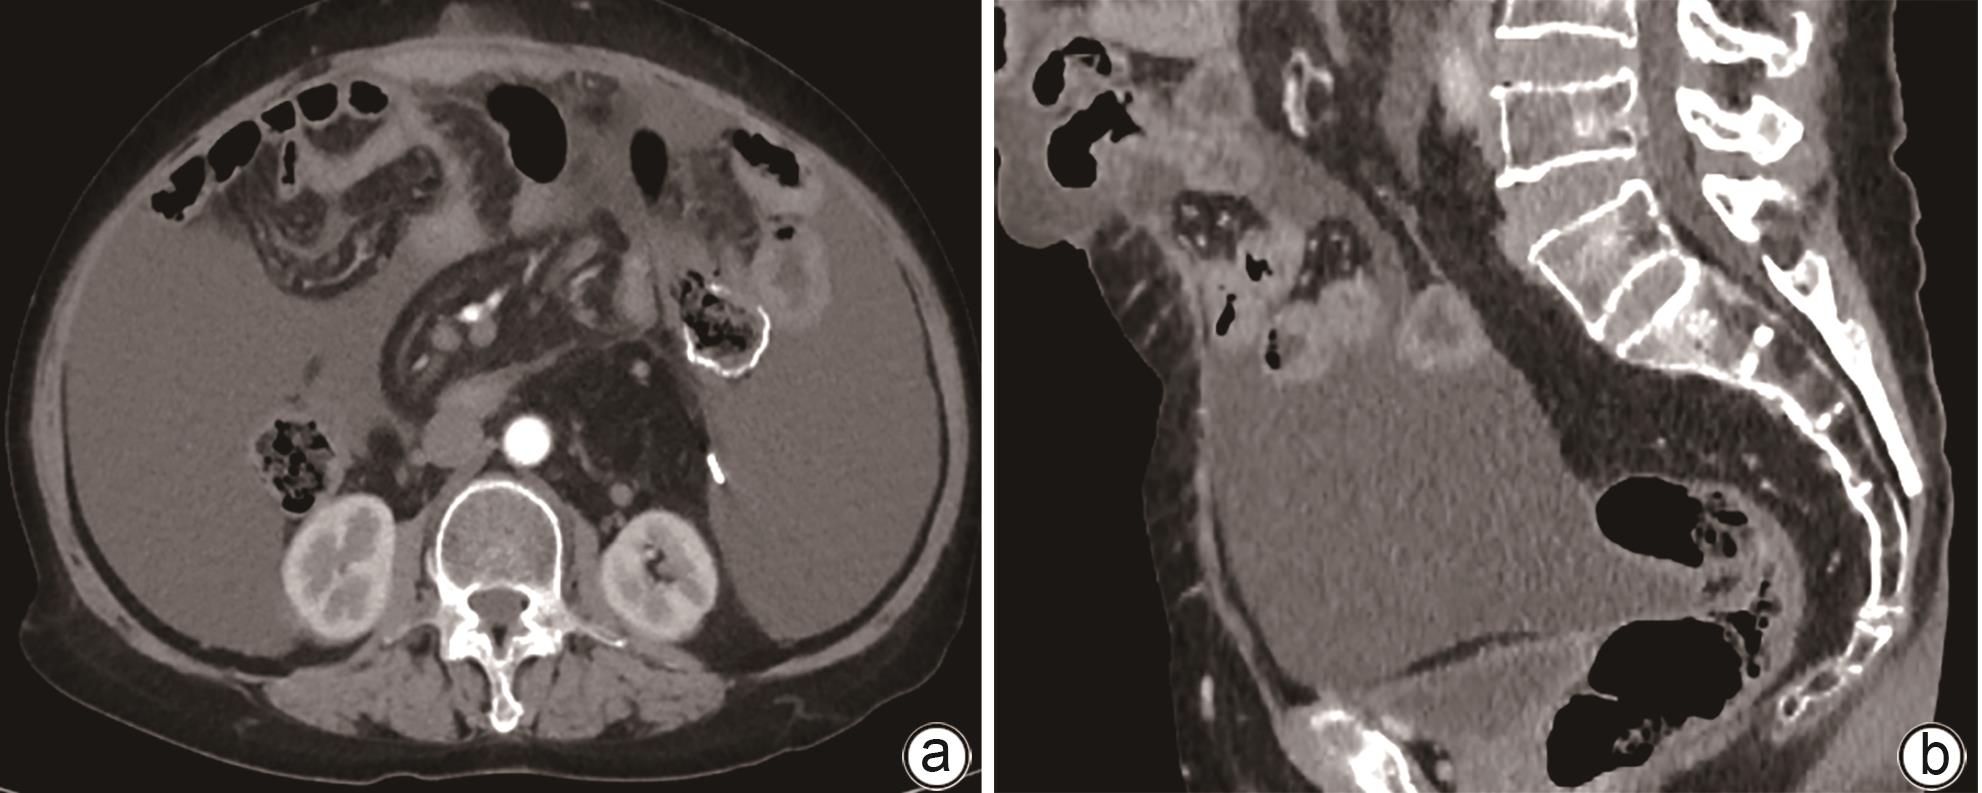

Diagnosis and treatment of decompensated cirrhosis with multiple primary cancers: A case report

2024, 40(9): 1868-1872. DOI: 10.12449/JCH240923

Abstract(927) HTML (392) PDF (1776KB)(108)

Abstract:

Multiple primary cancers (MPC) refer to the presence of more than one type of cancer with different histological features and sites in the same individual, and it is relatively rare in clinical practice. This article reports a case of decompensated cirrhosis with MPC and discusses the diagnosis, treatment, and clinical implications of this patient with decompensated cirrhosis and MPC.